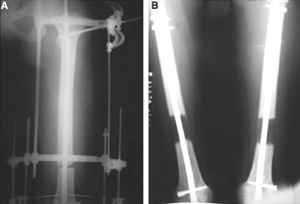

Коллеги! Прошу совета, какую тактику избрать при лечении.Больной 27 лет, мотоциклист. Поступил 23.04.10 ДЗ. О. перелом н.з левого бедра Gustillo 3b (c повреждение бедренной вены), О.Правого бедра Gustillo 2, з. фрагментарный перелом левой голени.При поступлении Hb 66 ISS 40, Фиксация стержневыми аппратами, сосудистые хирурги выполнили шов вены. Выполена резекция бедренной кости 9 см. На 7 сутки Желудочно-кмшечное кроветечение из стрессовых язв, 12 сутки флотирующий тромтоз 14 см установлен кава-фильтр. На 15 сутки закрытие ран местными тканями. Раны заживают первично. Воспаления на стержнях нет. В настоящий момент планируем. Переход со стержневых аппаратов на стержни с антибактериальным покрытием на правом бедре и левой голени. Левое бедро планируем продолжить фиксировать в стержневом аппарате.

Вопрос: что делать с левым бедром? Учитывая внутрисутавной характер перелома, дефект бедра 9 см.

Вчера перешли с аппаратов на стежни с аб покрытием на правом бедре и левой голени.

На левом бедре оставили аппарат бедро-голень.

Как вы думаете если сделать следующее.

После заживления раны на левом бедре. Выполнить открытую реподицию и синтез пластиной для дистального бедра. Пластину в проксимальном направлении зафиксировать монокортикально.

А затем выпонить остеотомию бедра в верхней трети.

И тракцию бедра на стержне. Типа (СМ картинки).

После выращивания регенерата стержень блокировать.